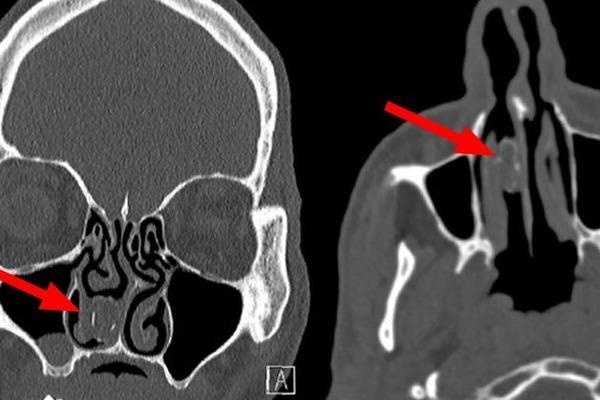

Người đàn ông mọc răng trong mũi

Thay vì mọc ở miệng, chiếc răng của người đàn ông 59 tuổi (Đan Mạch) lại mọc lạc trong mũi bởi chứng bệnh hiếm gặp.